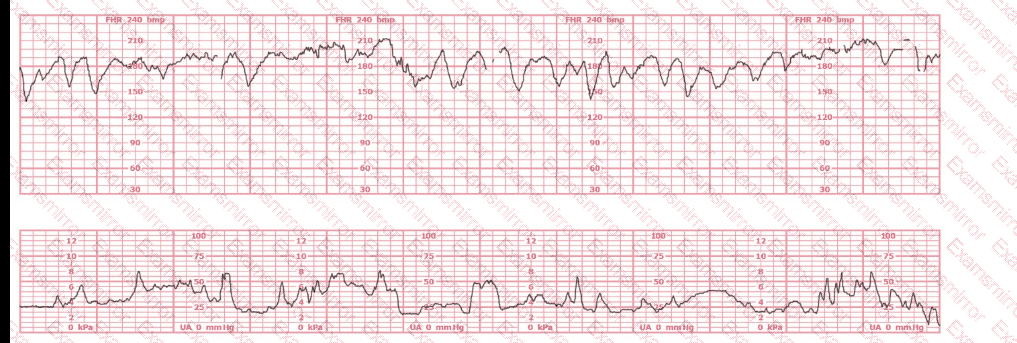

This is a tracing of a multiparous woman in the second stage of labor. The vertex is at +3 station. This pattern has continued for the last 20 minutes. She has been pushing for 2½ hours, and oxytocin is infusing at 12 milliunits/minute. Management should include